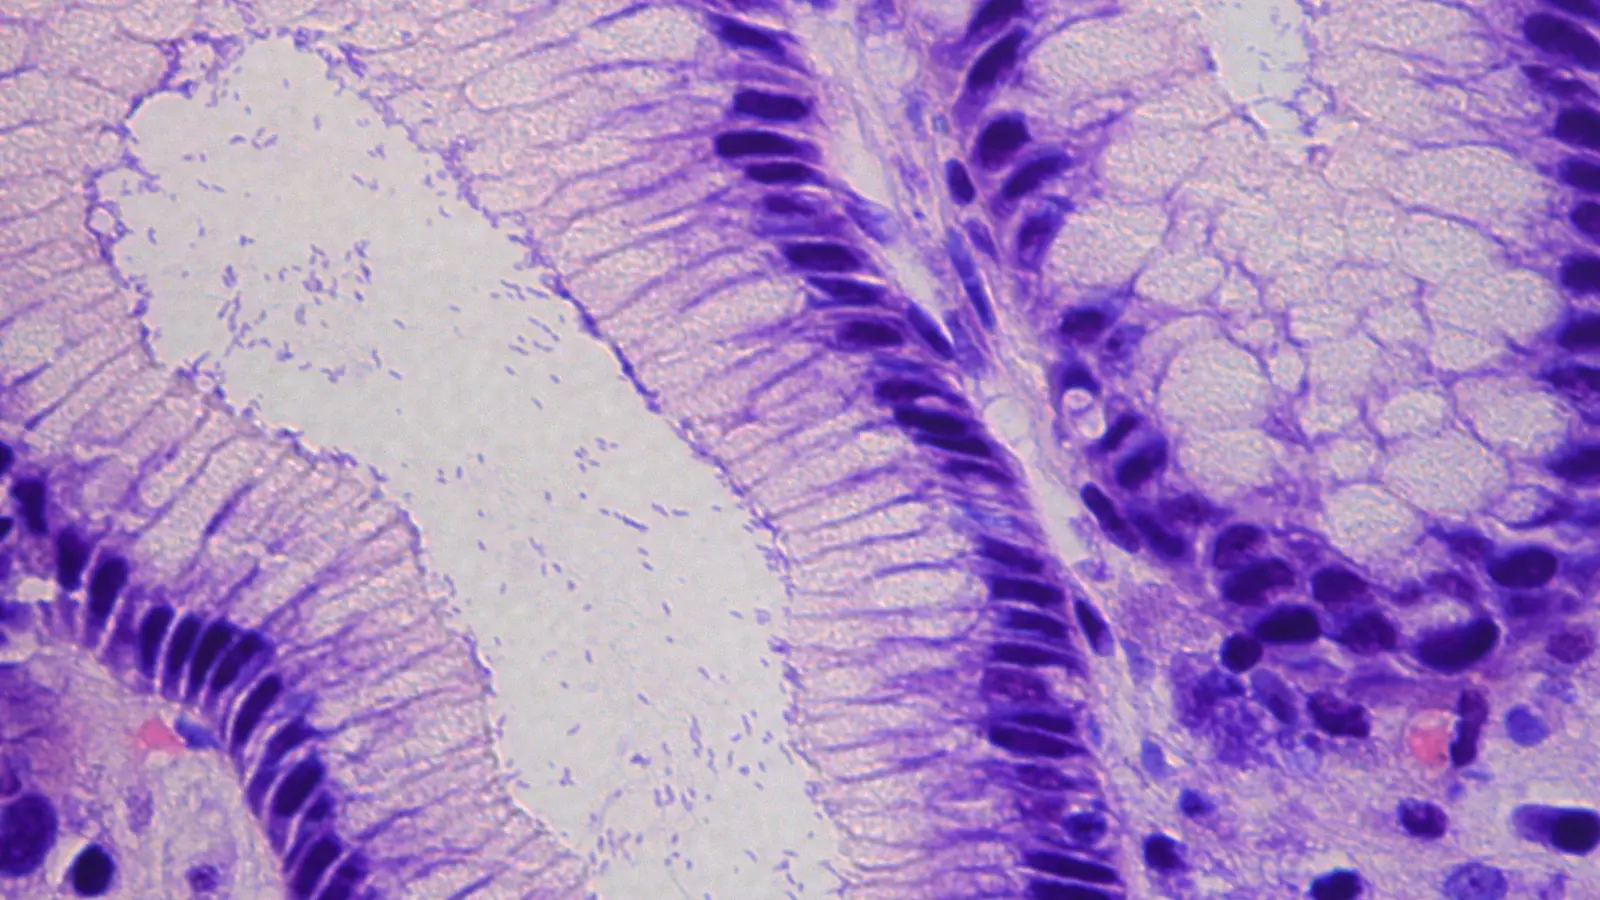

Weltweit sind rund 43 Prozent der Bevölkerung mit diesem Bakterium infiziert. Es kann chronische Magenschleimhautentzündungen verursachen, zu Magengeschwüren führen und gilt als zentraler Risikofaktor für Magenkrebs. Standardtherapien basieren vor allem auf dem Antibiotikum Metronidazol. Doch H. pylori wird zunehmend unempfindlich dagegen und entwickelt Resistenzen. Deshalb sind immer höhere hohe Dosierungen und Kombinationen mit weiteren Antibiotika nötig.